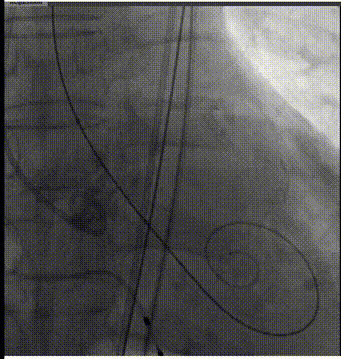

手术过程概览

主动脉根部造影

导丝跨瓣

球囊预扩

输送器过弓

输送器定位

瓣膜定位

瓣膜脱钩